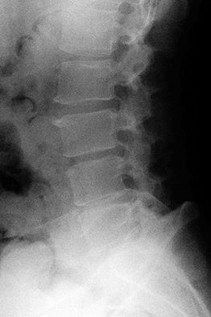

A 65-year-old female presents with neurogenic claudication and lower back pain. Radiographs reveal a grade I L4-L5 degenerative spondylolisthesis. Which of the following anatomical features is most characteristic of degenerative spondylolisthesis compared to isthmic spondylolisthesis?

Options:

- Defect in the pars interarticularis

- Sagittal orientation of the facet joints

- Association with a high pelvic incidence and sacral slope

- Predilection for the L5-S1 level

- Presentation typically in the second decade of life

Correct Answer: Sagittal orientation of the facet joints

Explanation:

Degenerative spondylolisthesis most commonly occurs at L4-L5 and is associated with a more sagittal orientation of the facet joints, which allows for anterior translation as the disc and joints degenerate without a pars defect. Isthmic spondylolisthesis involves a pars interarticularis defect, most commonly occurs at L5-S1, and is often associated with higher pelvic incidence.